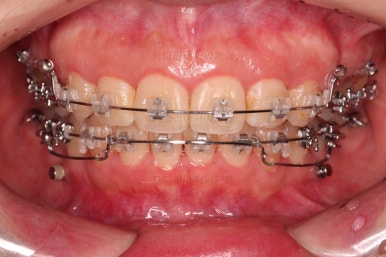

장치를 부착합니다.

이번 환자분이 선택한 장치는 엠파워 클리어라고 하는 자가결찰 세라믹 장치인데요.

철사를 묶는(결찰) cap이 장치에(자가) 달려있는 장치 중에 세라믹 성분으로 되어 심미성이 우수한 브라켓입니다.

대표적으로는 클리피씨 장치 등이 있습니다.

우선은 적응을 위해서 윗니만 장치를 부착하고요.

아랫니는 과개교합 개선을 위해 앞니 먼저 시작합니다.